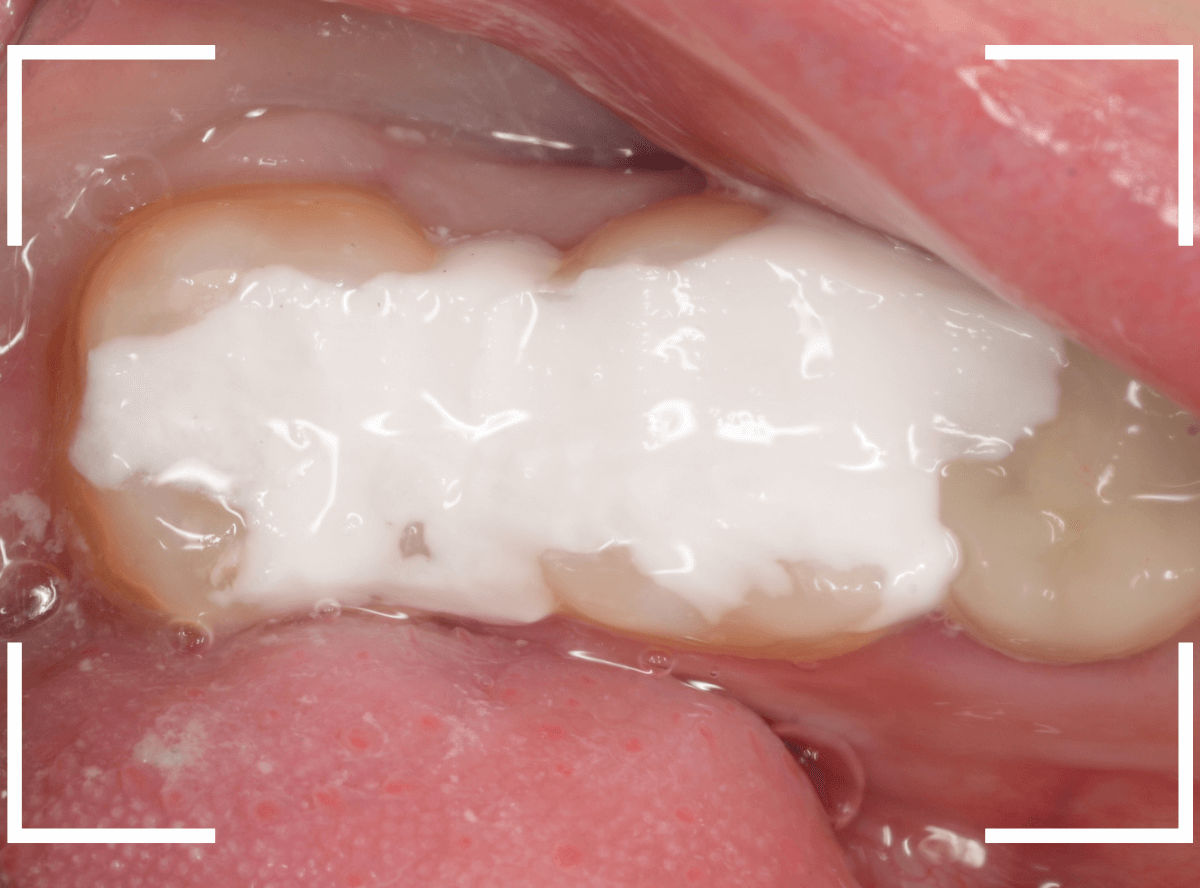

Case.2 症状がないけど、神経が見えるほどの虫歯!

こちらも別の歯の治療を目的に受診された方です。

特に症状もないため、本人には全く自覚はありませんが、一目見てわかるほど歯と歯の間に大きな虫歯があります。

治療をすると、やはり大きな虫歯が出てきました。

まだまだ虫歯は深いです。

かなり大きく削りましたが、まだ虫歯が残っているのがわかります(赤く染まっている部分)。

慎重に虫歯を除去し、神経ギリギリのところで虫歯をくいとめました。

しかし、手前の歯をよく見ると、神経がうすく透けて見える状態ですので、本当にギリギリです。

このような深い状態の虫歯でも、症状がなく、治療後に痛み出す事もあります。

今回もお薬をつめて、お痛みが出ないかしばらく経過観察となりました。

虫歯を見た目や痛みなどの自覚症状だけで問題ないと自己判断する患者さんがいます。

「痛みのない、問題ない歯を削られた!」と騒ぐ方もいます。

このような症例を見る事によって、症状がなくても歯科医院でしっかり定期検査し、治療を受ける重要性を理解していただければと思います。